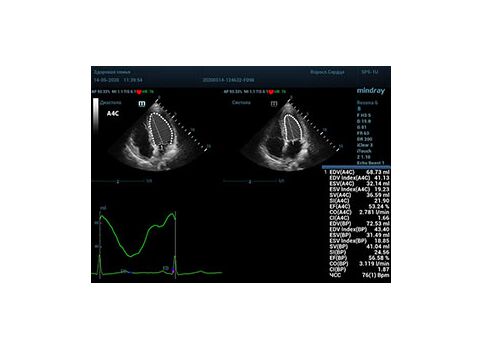

С появлением В режима реализовалась возможность визуализации всех сегментов миокарда из парастернальных и апикальных сечений. Метод Teicholtz в широкой практике сменился методом дисков. Метод дисков, или метод Simpson, позволяет разбить левый желудочек на 20 дисков, с расчетом объема каждого из них. Используя 2 перпендикулярных сечения, апикальные двух и четырех камерное, мы приближаемся к значению реального объема левого желудочка. Исследователь обводит интерфейс эндокард – кровь в фазу диастолы и фазу систолы. Линия простирается от кольца митрального клапана и до кольца митрального клапана, четко разграничивая объем желудочка от предсердия. Для достоверного изменения необходимо использовать ЭКГ канал.

Обводить вручную эти линии занимало много времени, однако результат того стоил. Следующим шагом стало появление Spline технологии, позволяющее расставлять точки и автоматически их соединять. Такой способ планиметрии контура эндокарда значительно сократил время измерения.

Что могут предложить современные приборы? Приборы нашего времени являются мощными вычислительными машинами, способными обрабатывать полученную информацию даже без помощи человека. Система автоматического вычисления фракции выброса – AUTO EF на приборах серии Resona компании Mindray сделает все за вас. За пару секунд прибор сам отыщет нужную фазу сердечного цикла и произведёт измерение и расчеты, а также покажет график изменения объема в сердечном цикле. От Вас требуется только получить качественное 4С и 2С сечение. Впрочем, прибор всегда оставляет возможность коррекции, если доктор имеет свое мнение на расположение точек планиметрии или момента измерения по ЭКГ каналу.